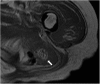

Hamartomas are tumours composed of mesenchymal tissues such as cartilage, fat, connective tissue and smooth muscle and can be found in virtually any organ system. These masses commonly develop sporadically, but are also seen in certain syndromes such as tuberous sclerosis or Carney triad. While their imaging appearance varies depending on the organ they arise from, findings are usually unique and a diagnosis can be confidently made. Radiologists must be aware of the clinical and imaging presentations of these lesions with the particular goal of avoiding unnecessary studies or invasive procedures. Furthermore, knowledge of common syndromic entities is crucial, as the radiologist may be the first to suggest the diagnosis.